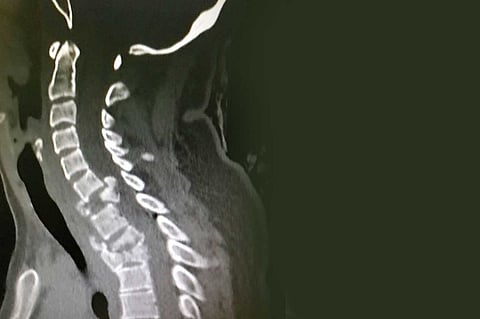

وذكر بيانٌ صادرٌ عن «صحة القصيم» اطلعت عليه «عاجل»، أن الحادث الذي تعرضت له الشابة (26 عامًا) أصابها كذلك بضعف الحركة في الأطراف العلوية ووجود «رض» بالنخاع الشوكي الرقبي، وكسر مفتت بالفقرة الرقبية السابعة، وكسر مستقر بالفقرتين الظهريتين الثانية والثالثة.

وفور وصول المريضة إلى قسم الطوارئ، باشر أطباء الطوارئ وأطباء الجراحة بقيادة استشاري جراحة المخ والأعصاب الدكتور عبدالله السويري حالة المصابة، وتم إجراء الفحوصات الطبية وعمل الأشعة اللازمة.

وقرر الأطباء، بحسب البيان، وضع المريضة على الشد الرقبي لمدة ثلاثة أيام؛ حيث كان هناك انغماس رئوي أيسر، وبعد أن استقرت الحالة تم نقلها إلى غرفة العمليات، وأجريت لها عملية استئصال الفقرة السابعة كاملة، ووضع بدلًا منها ما يسمى بـ«ميش» مع طعم عظمي وصفيحة وبراغي بين الفقرات، وإزالة كامل الضغط عن النخاع الشوكي الرقبي.